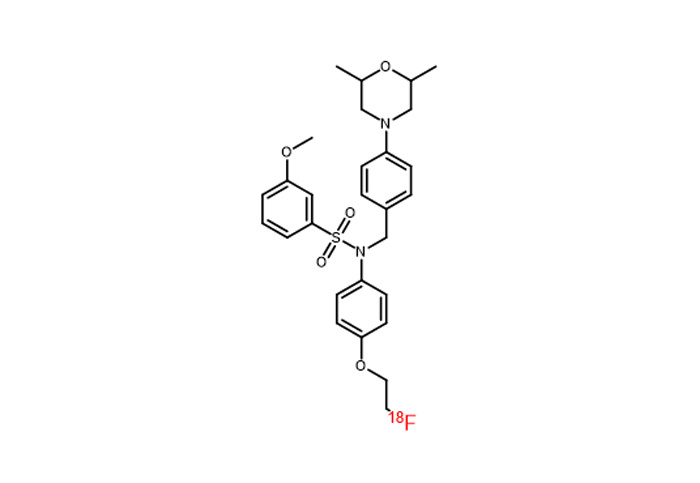

對(duì)18F、11C、68Ga、等核素示蹤劑的(de)合成與國(guó)外(wài)主流示蹤劑合成平台達到(dào)同一(yī)水(shuǐ)<平;